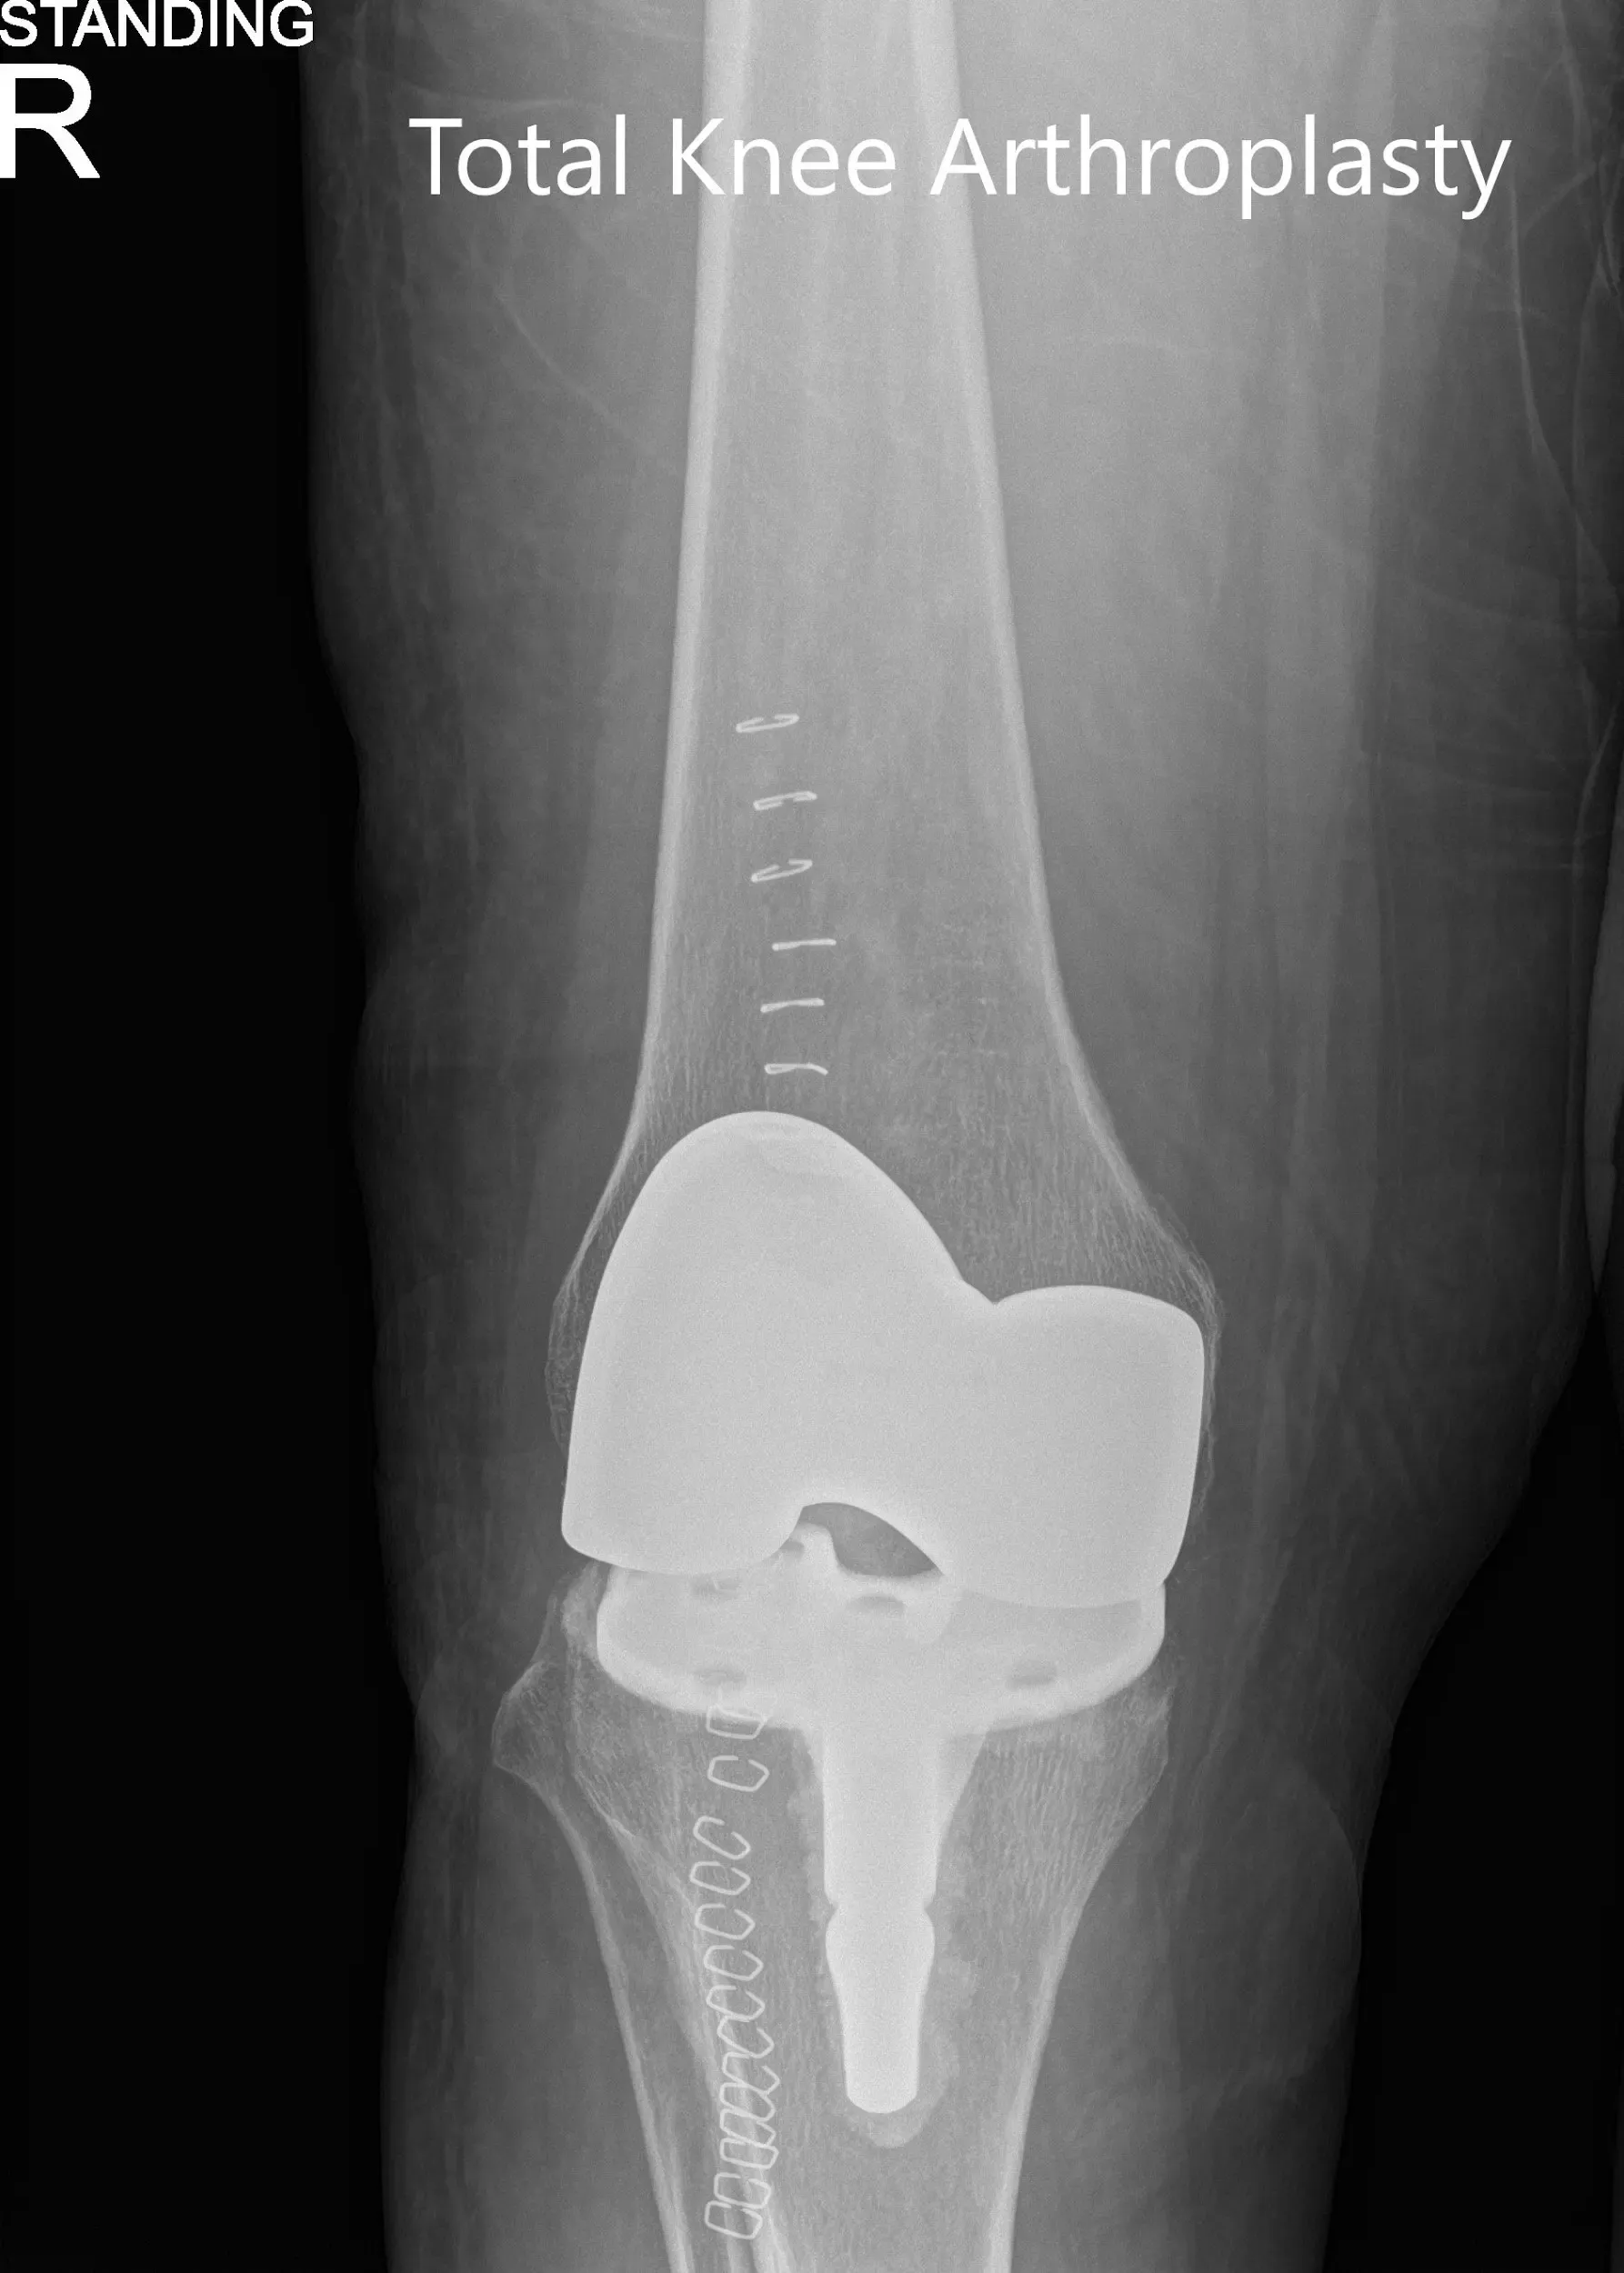

Radiografía postoperatoria que muestra las vistas anteroposterior y lateral de la rodilla derecha.

Después de la operación tuvo una recuperación excelente. Ella pudo ponerse de pie y caminar el mismo día del procedimiento. El dolor se manejó bien con medicación. Recibió fisioterapia ambulatoria y cumplió con el programa de ejercicios en casa. Se administró aspirina para la profilaxis de la trombosis venosa profunda.

Tres meses después de la operación mostró un rango de movimiento completo sin dolor. Caminaba sin apoyo y reportó su estado a su estado base. Estaba extremadamente contenta con el resultado.